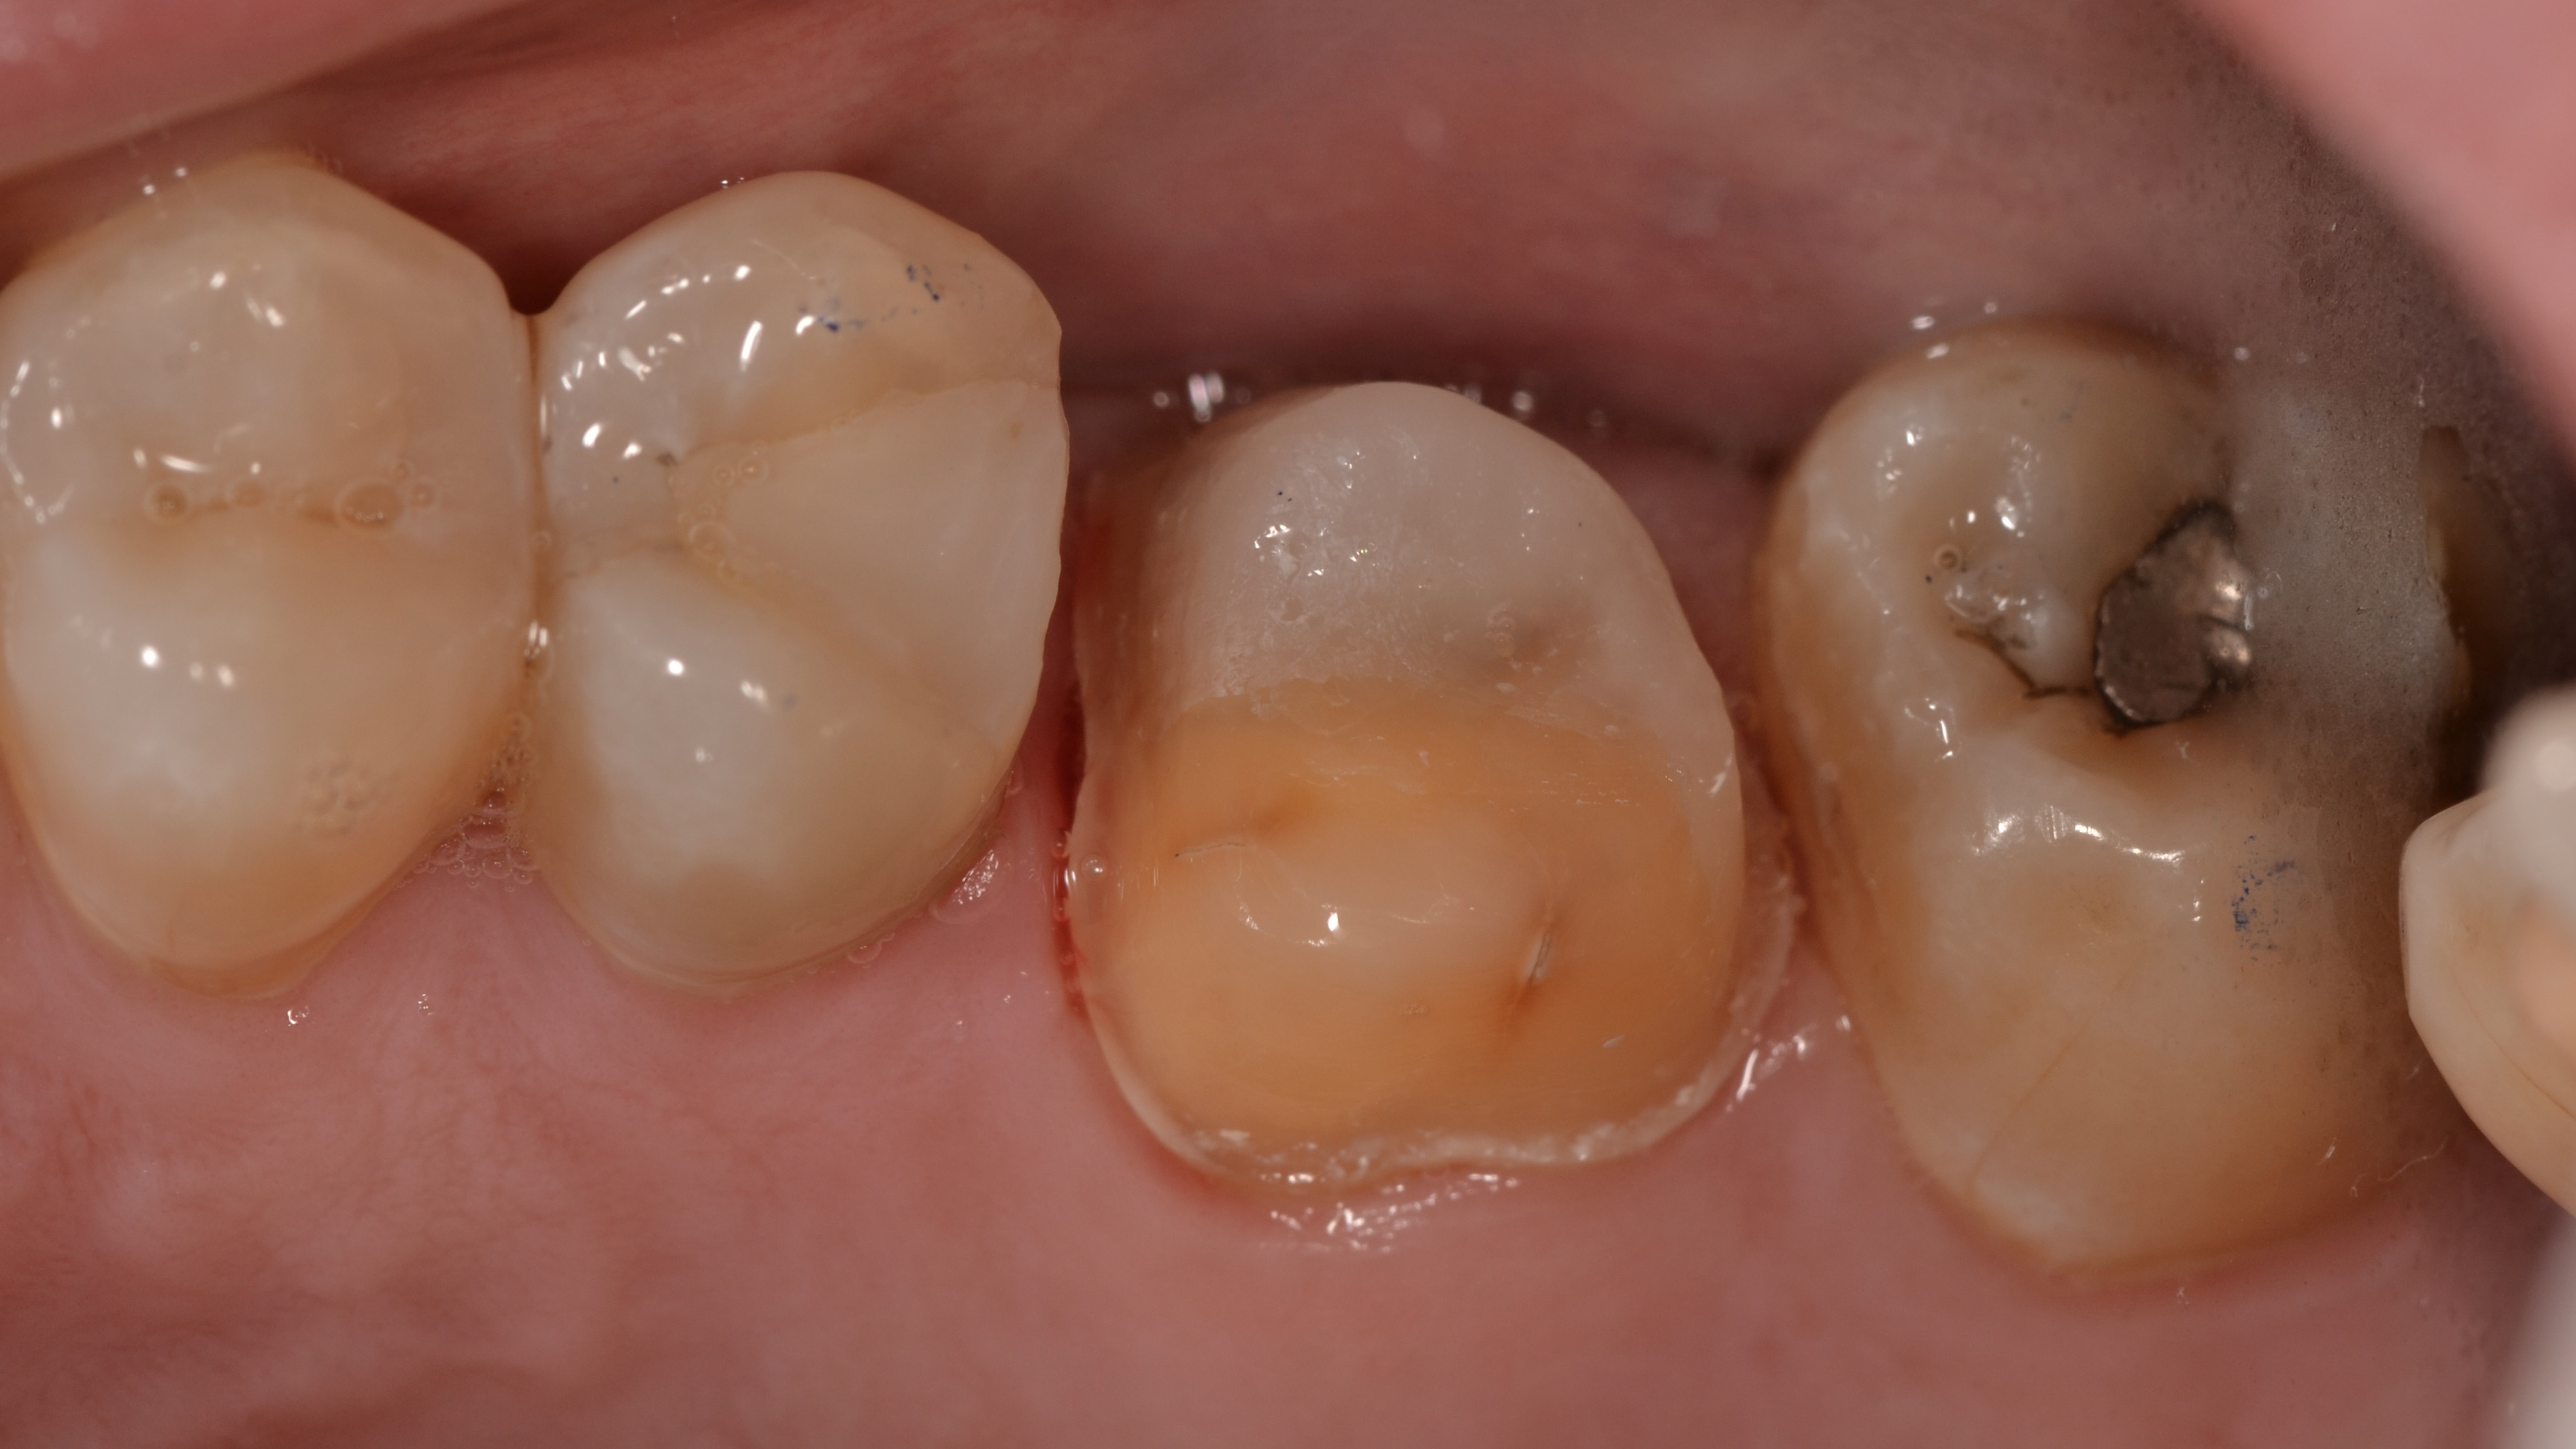

Cavity Broken Metal Filling

Fractured Tooth and Broken Metal Filling